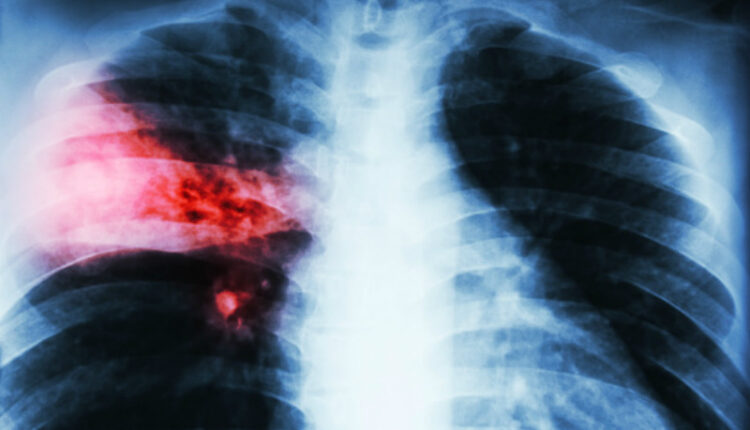

ସଂକ୍ରମଣ ଯୋଗୁଁ ଗୋଟିଏ ବା ଦୁଇଟି ଯାକ ଫୁସଫୁସ ରେ ପ୍ରଦାହ ଜାତ ହୁଏଓ ଫୁସଫୁସ ଭିତରେ ଥିବା ବାୟୁ ସ୍ଥଳୀରେ ତରଳ ପଦାର୍ଥ ଜମିଯାଏ। ଫଳରେ ଫୁସଫୁସ ଠିକ୍‍ ଭାବେ କାର୍ଯ୍ୟ କରେ ନାହିଁ । ୨ରୁ ୫ବର୍ଷର ପିଲାମାନେ ଏହି ରୋଗରେ ପୀଡିତ ହୁଅନ୍ତି । କାରଣ ସେମାନଙ୍କର ପ୍ରତିରୋଧକ ଶକ୍ତି ଦୁର୍ବଳ ଥାଏ । କେବଳ ବର୍ଷାରେ ଭିଜିଲେ ଯେ ନିମୋନିଆ ହୁଏ ତାହା ନୁହେଁ । ତାପମାତ୍ରାରେ ପରିବର୍ତ୍ତନ ଯୋଗୁଁ ମଧ୍ୟ ନିମୋନିଆ ହୋଇପାରେ । ଓଦାଳିଆ ପରିବେଶ,ବାୟୁ ପ୍ରଦୂଷଣ,ଧୂମପାନ ଏବଂ ଜନଗହଳି ବ୍ୟାକ୍ଟରିଆ ଭୂତାଣୁ ଓ କବକ ମାନଙ୍କ ବଂଶବୃଦ୍ଧିର କାରଣ ହୋଇଥାଏ ।